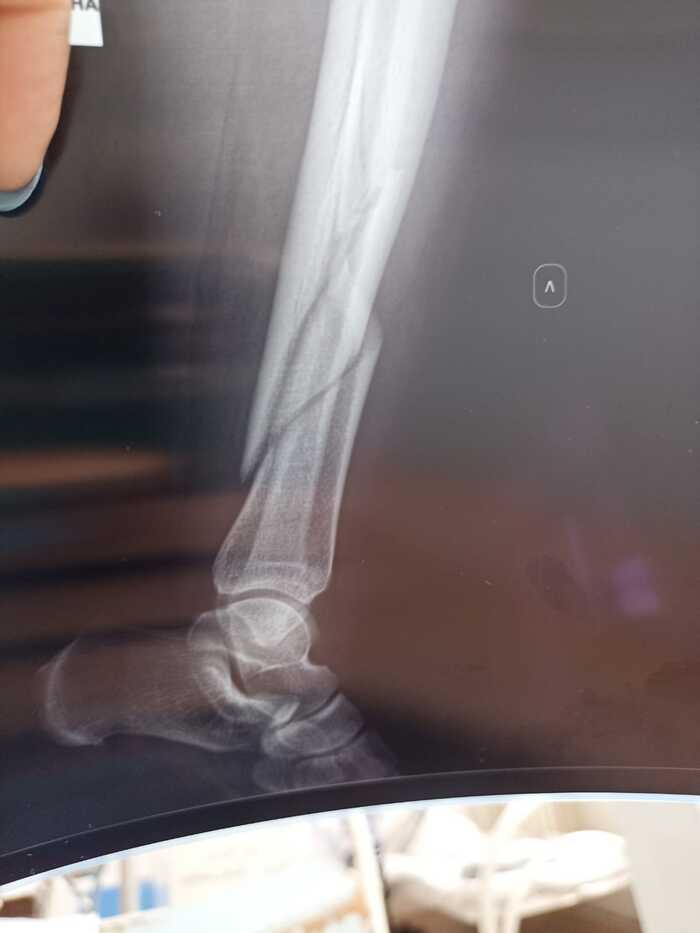

Ограничитель двери и испорченный отпуск

Не думал что мой первый пост будет вот про это вот все, но господин несчастный случай заставил написать.

Приехали мы с женой и ребёнком отдыхать к родителям и возвращаясь в один из августовских вечеров домой, моя жена в потёмках спотыкается у двери в подъезд об ограничитель открытия двери подъезда. Итог - бессонная ночь, испорченный отпуск и самое страшное - перелом обоих костей голени левой ноги. Вопрос к юристам, подскажите могу ли я привлечь управляющую компанию к ответу за это безобразие?